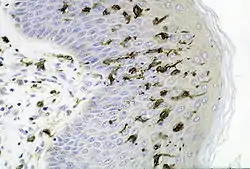

Dendritic cells in skin | |